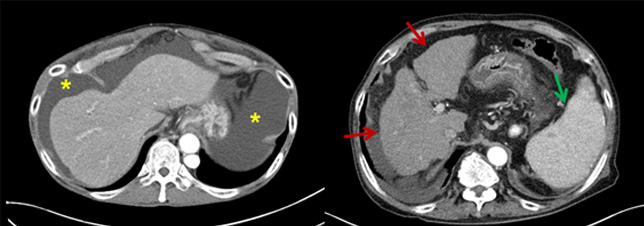

- 병리조직학적으로 정의되는 질환으로 임상적으로 대상성 간경변증과 비대상성 간경변증으로 분류되며 비대상성 간경변증은 복수, 정맥류 출혈, 간성뇌증, 황달이 있는 경우로 정의할 수 있습니다.

- 진단은 주로 임상적으로 이루어 지며, 문진, 신체검사, 영상검사와 피검사등이 필요합니다.

- 원인으로는 만성 B, C형 간염, 알코올성 간염, 비알코올성 지방간, 원발성 담즙성 간경병증등이 있으며, 흔하지 않은 유전적, 대사성 간질환도 있습니다.

- 합병증은 식도, 위 정맥류 출혈, 간경변성 복수, 간성뇌증, 간신증후군, 간암의 발생이 있습니다.